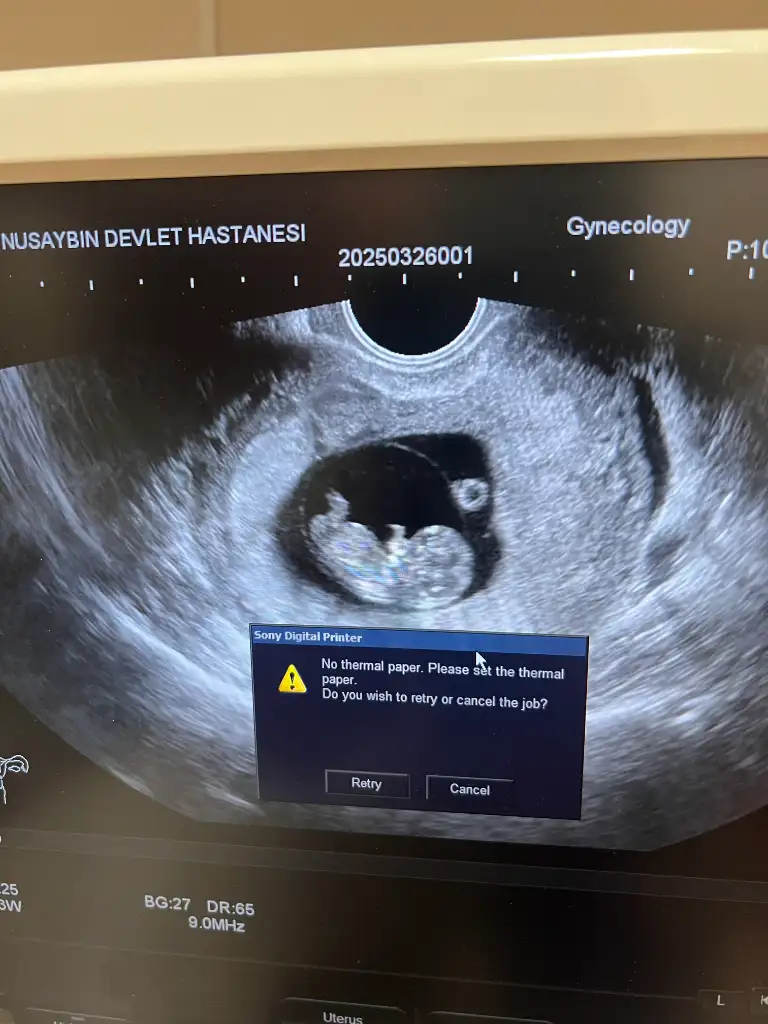

8+5 Vajinal bakıldı cinsiyet tahmini bana da yapın lütfen

Eklentiler

• IMG_4081.webp

IMG_4081.webp

42,3 KB · Görüntüleme: 93